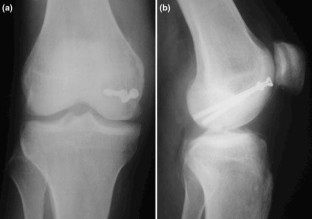

Nonunion of a Hoffa fracture in an adult

The coronal fractures of femoral condyles, known as Hoffa fractures, are a rarity. Conservative management often leads to unsatisfactory results and nonunion. In this study, we present a case of a 35-year-old patient with an established nonunion of medial Hoffa fracture of right knee treated with open reduction and internal fixation.

Fig. 1